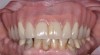

The clinician should review and reinforce with the patient the patient-administered oral hygiene efforts. Use of an intraoral stain to demonstrate inadequate plaque control has been shown to be effective in patient motivation.19 Nonsurgical peri-implant treatment should consist of mechanical removal of the bacterial biofilms and elimination or control of all local plaque retentive factors. Curettes, sonic and ultrasonic instruments, as well as air polishing with glycine powder are all effective methods of biofilm removal.20 The use of local antibacterials and local or systemic antibiotics appear to have minimal benefit.21 Once the treatment of peri-implant mucositis has been rendered, it is very important that the oral healthcare provider evaluate the response to therapy (Figure 3 and Figure 4). If initial therapy fails to resolve the peri-implant inflammation, it may be beneficial to assess the marginal fit and design of the implant prosthesis with regard to patient access, as well as the possible presence of cement remnants.

Fig 3. Nonsurgical peri-implant treatment was performed, and the existing prosthesis was modified to enable access for patient-administered oral hygiene.

Figure 3

Fig 4. Four weeks after treatment, the patient presented with healthy peri-implant tissues.

Figure 4